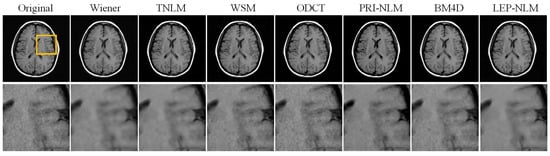

3.2. Real MR Images